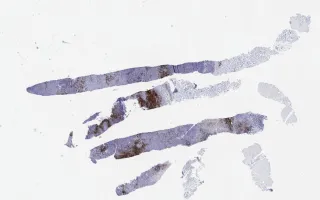

Lymph Nodes, Kikuchi-Fujimoto disease, CD123 stain

Kikuchi-Fujimoto disease

30 year old female, with one month history of cervical lymphadenopathy.

Kikuchi-Fujimoto disease, also known as histiocytic necrotizing lymphadenitis, is an inflammatory process of unknown etiology. It commonly affects young patients (